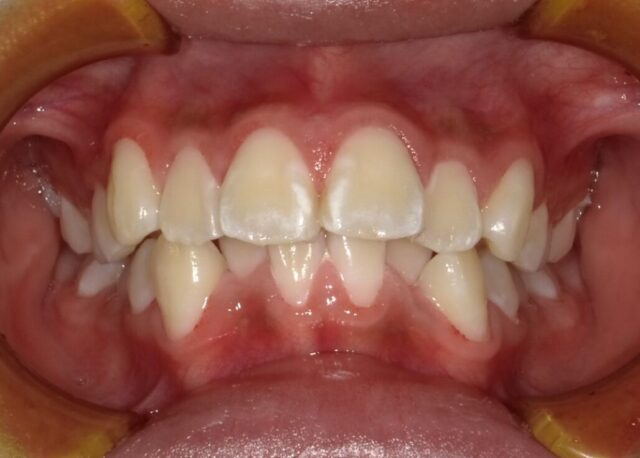

2024年6月(12歳8ヶ月)

永久歯揃いました。

本人のやる気がでたら

2段階目スタートします。